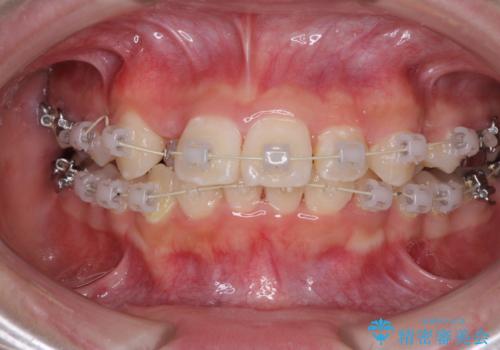

インビザラインが続けられない ワイヤー矯正での抜歯矯正 その2

- 八重歯やデコボコをインビザラインで治療したいとのことで来院された患者様です。

インビザライン単体で治療を行うには叢生が強いと判断されたため、事前にワイヤー装置で抜歯矯正を行い、ある程度改善してからインビザラインにて仕上げていくこととしました。